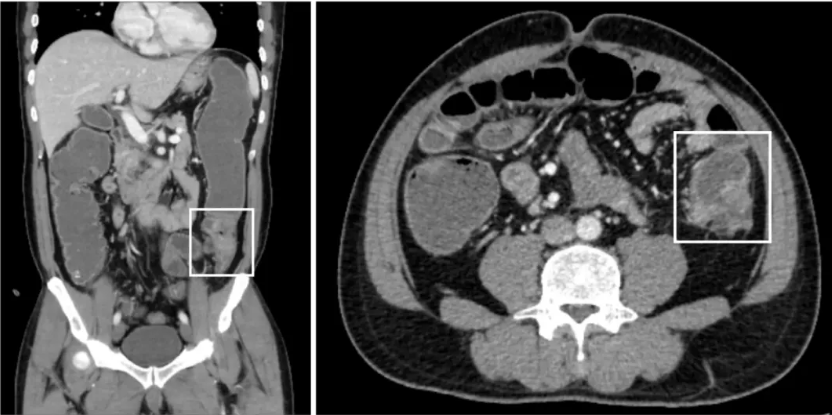

患者5天前无明显诱因出现脐周绞痛、腹胀及排气排便停止,遂前往当地医院就诊。腹部CT检查显示乙状结肠上段肠壁增厚、近端肠管扩张及不完全肠梗阻,高度怀疑结肠癌(图1)。保守治疗后病情未见好转,患者遂转诊至中山大学孙逸仙纪念医院继续接受治疗。

图1. 患者入院时的CT图像

入院初,全腹及盆腔CT扫描显示乙状结肠上段肠壁增厚,表面粗糙,病灶管腔狭窄。周围淋巴结、肝脏及直肠系膜筋膜未见明显转移征象。在接受FOLFOXIRI治疗期间,MRI和PET-CT显示病情进展:直肠系膜筋膜内出现一个新结节(10 mm×10 mm),肝Ⅳ/Ⅷ段存在一个可疑病变(10 mm×9 mm),均考虑为转移瘤。